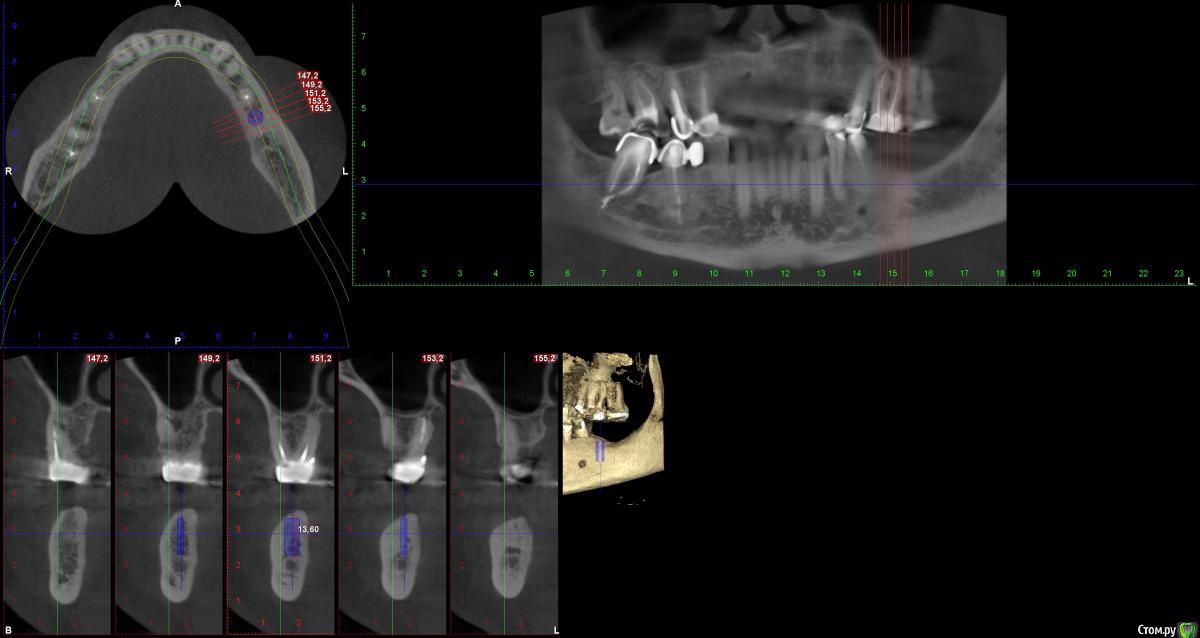

indie Опубликовано 4 октября, 2018 Поделиться Опубликовано 4 октября, 2018 Здравствуйте, колеги. Решил заняться имплантацией, думал выбирать только идеальные случаи, по Гудману так сказать. Но таких оказалось не больше 1-2 месяц, потому взялся за не совсем идеальные. По этой причине нужна помощь опытных врачей в планировании и прогнозировании возможных осложнений. Пац. 52 года. КТ прилагаю . Планируются имплантанты в позицию 36 37 MIS C1. 36 - 4.2x10mm, 37-5x8mm. Что смущает, во первых вертикальный дефицит твердых и мягких тканей, особенно в зоне 37, во вторых стоит ли вообще ставить имплантат в позицию 37. Если ставить, то можно ли обойтись без аугментаций? Ну и вообщем интересно, какой стратегии держатся в подобных не идеальных ситуациях? Спасибо. Ссылка на комментарий

TIGER Опубликовано 4 октября, 2018 Поделиться Опубликовано 4 октября, 2018 Здравствуйте, колеги. Решил заняться имплантацией, думал выбирать только идеальные случаи, по Гудману так сказать. Но таких оказалось не больше 1-2 месяц, потому взялся за не совсем идеальные. По этой причине нужна помощь опытных врачей в планировании и прогнозировании возможных осложнений. Пац. 52 года. КТ прилагаю . Планируются имплантанты в позицию 36 37 MIS C1. 36 - 4.2x10mm, 37-5x8mm. Что смущает, во первых вертикальный дефицит твердых и мягких тканей, особенно в зоне 37, во вторых стоит ли вообще ставить имплантат в позицию 37. Если ставить, то можно ли обойтись без аугментаций? Ну и вообщем интересно, какой стратегии держатся в подобных не идеальных ситуациях? Спасибо. М..jpg1.jpgМ.1.jpg36 берите 8мм,это конус,нужно будет заглублять Ссылка на комментарий